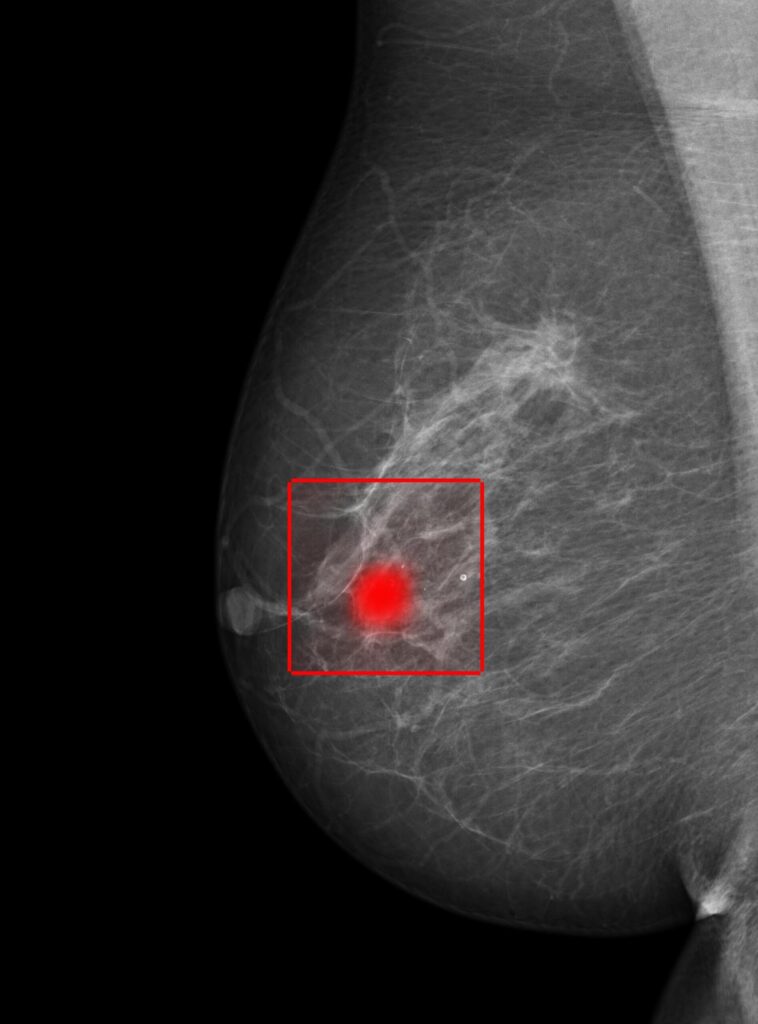

Arbeidet vårt spenner fra brystkreftdeteksjon i mammogrammer til automatisert analyse av hjerteultralyd.

Når analysene bygger på forklarbar KI, det vil si modeller som synliggjør hvilke funn og mønstre som ligger til grunn for en vurdering, får legene ikke bare et resultat, men også innsikt i hvordan modellen har kommet fram til konklusjonen. Dette er viktig for klinisk tillit og etterprøvbarhet.

Grafkonvolusjonelle modeller kan identifisere nøkkelområder i brystet og gi radiografer umiddelbar tilbakemelding under avbildning, for eksempel ved feil posisjonering.